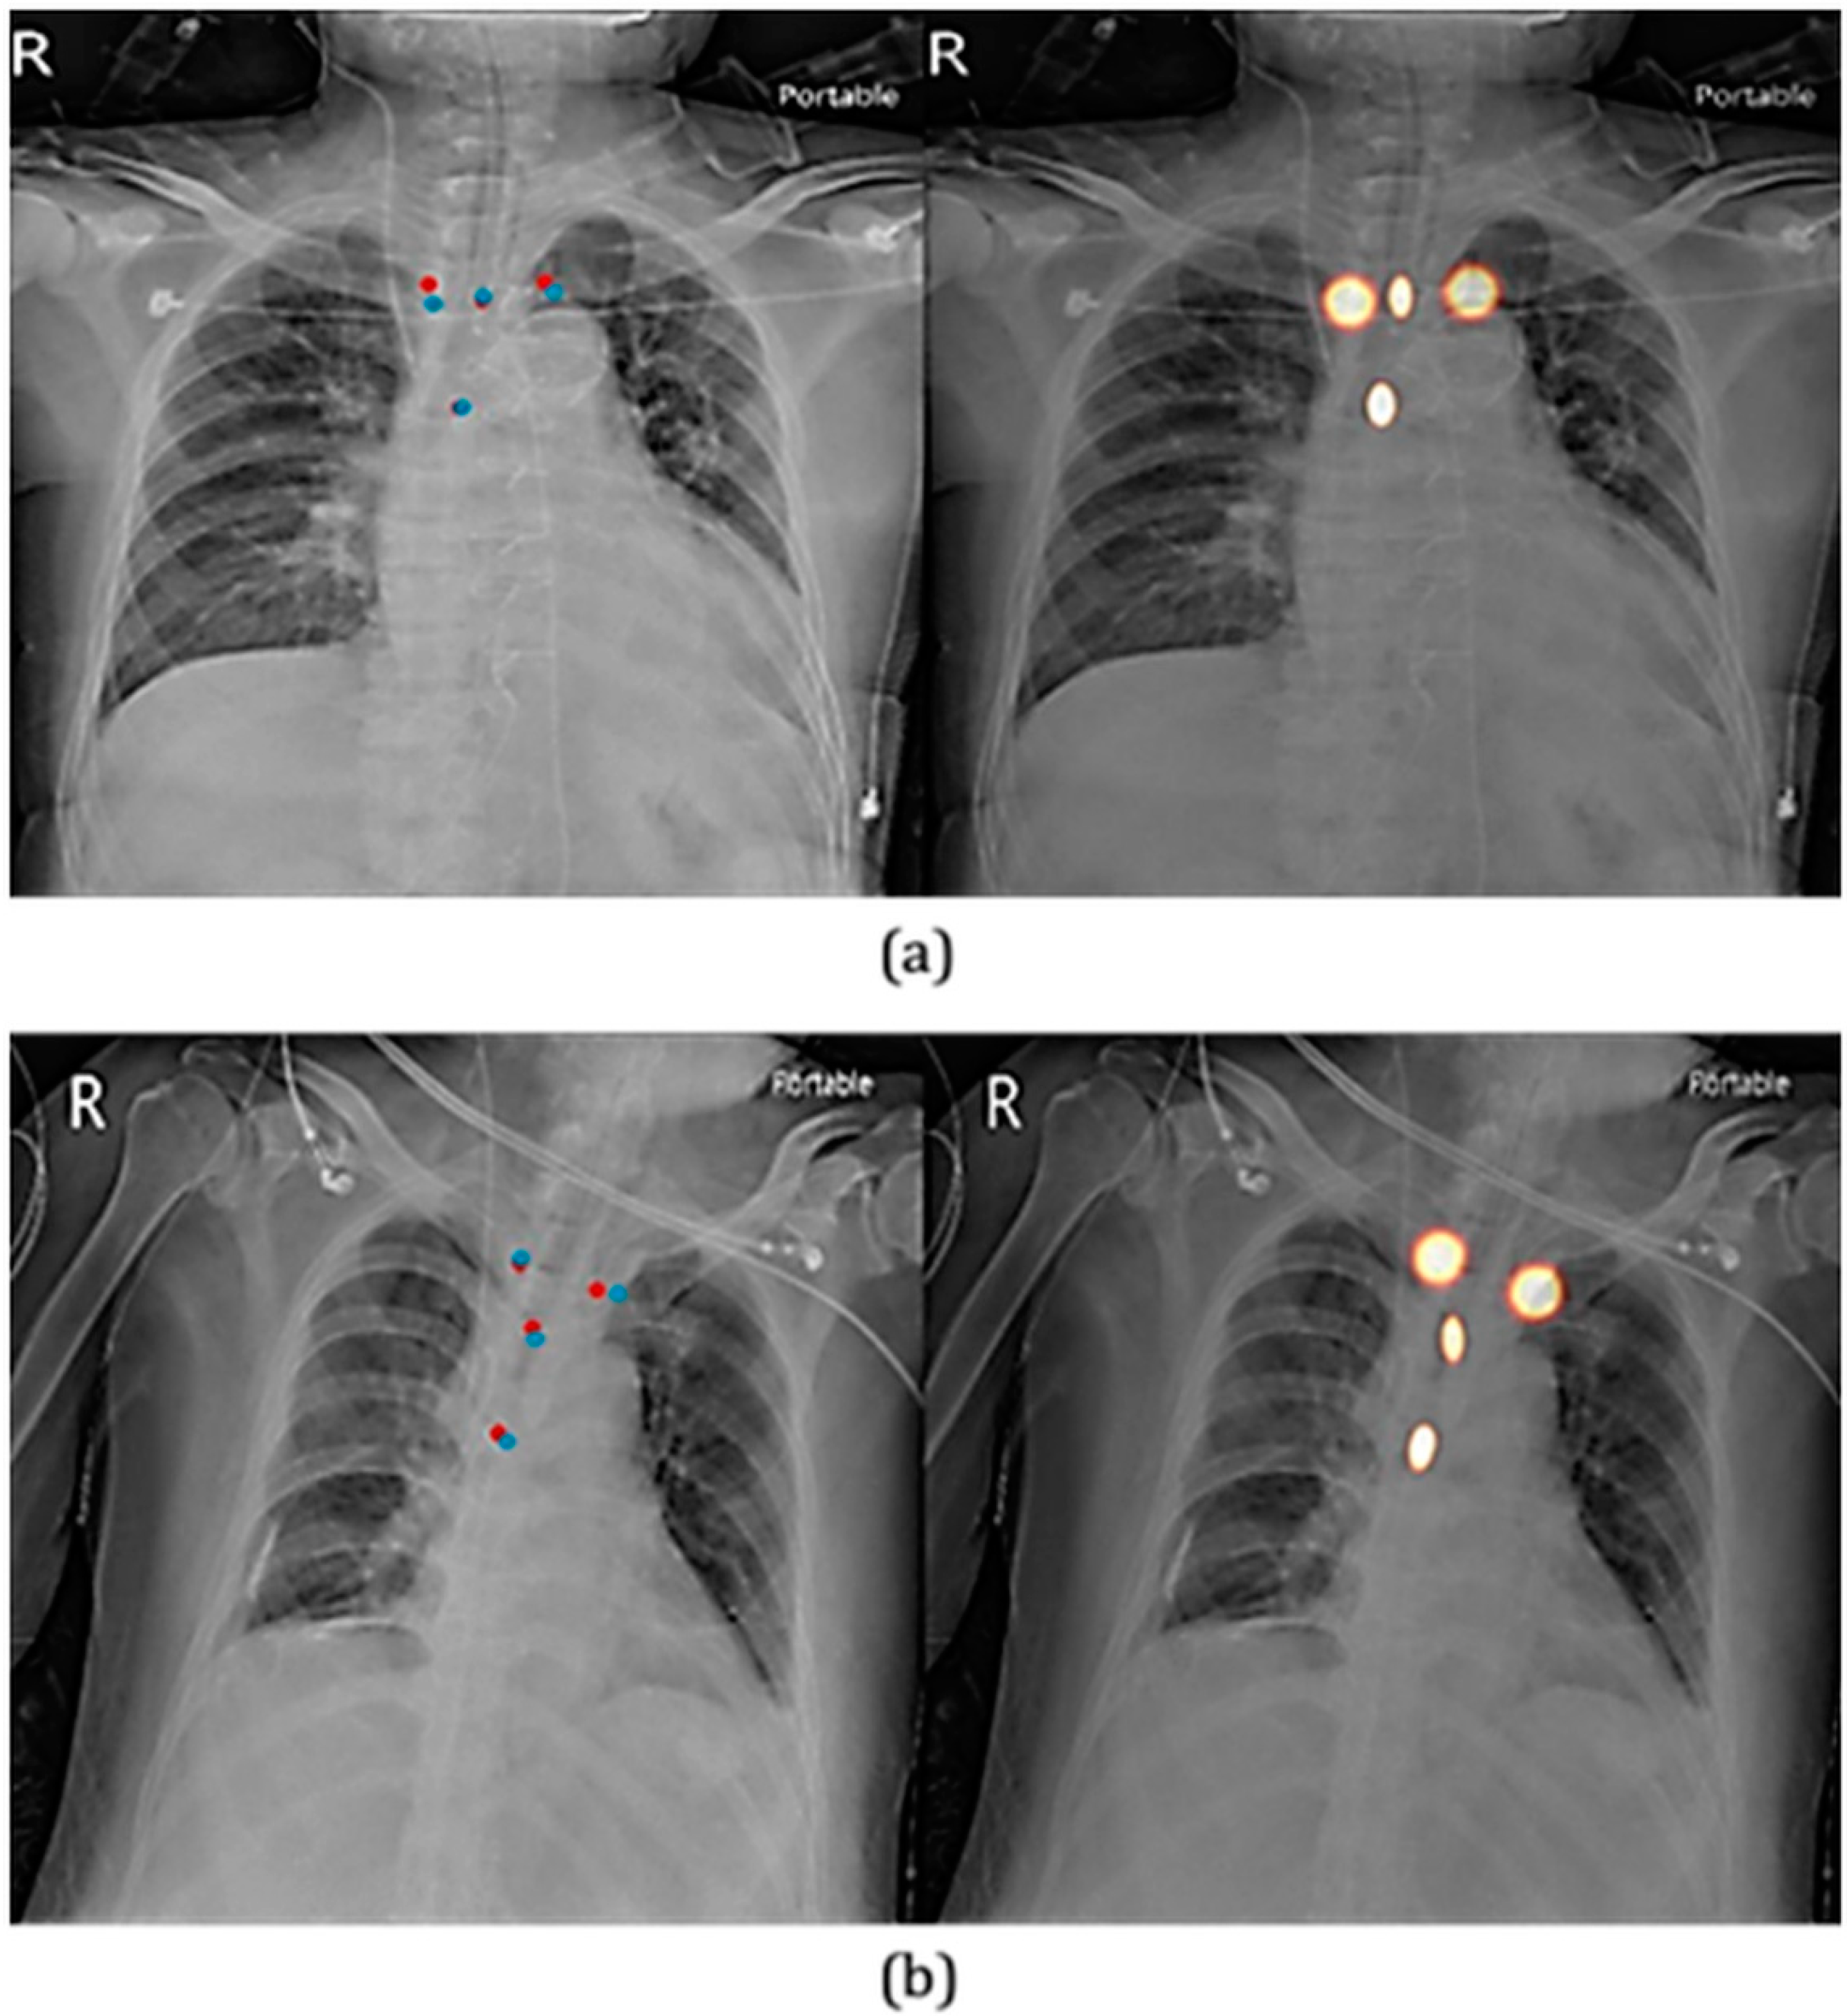

2.3.1. The First Component: Two-Stage Key Point Detection Model

3.1. Key Point Detection